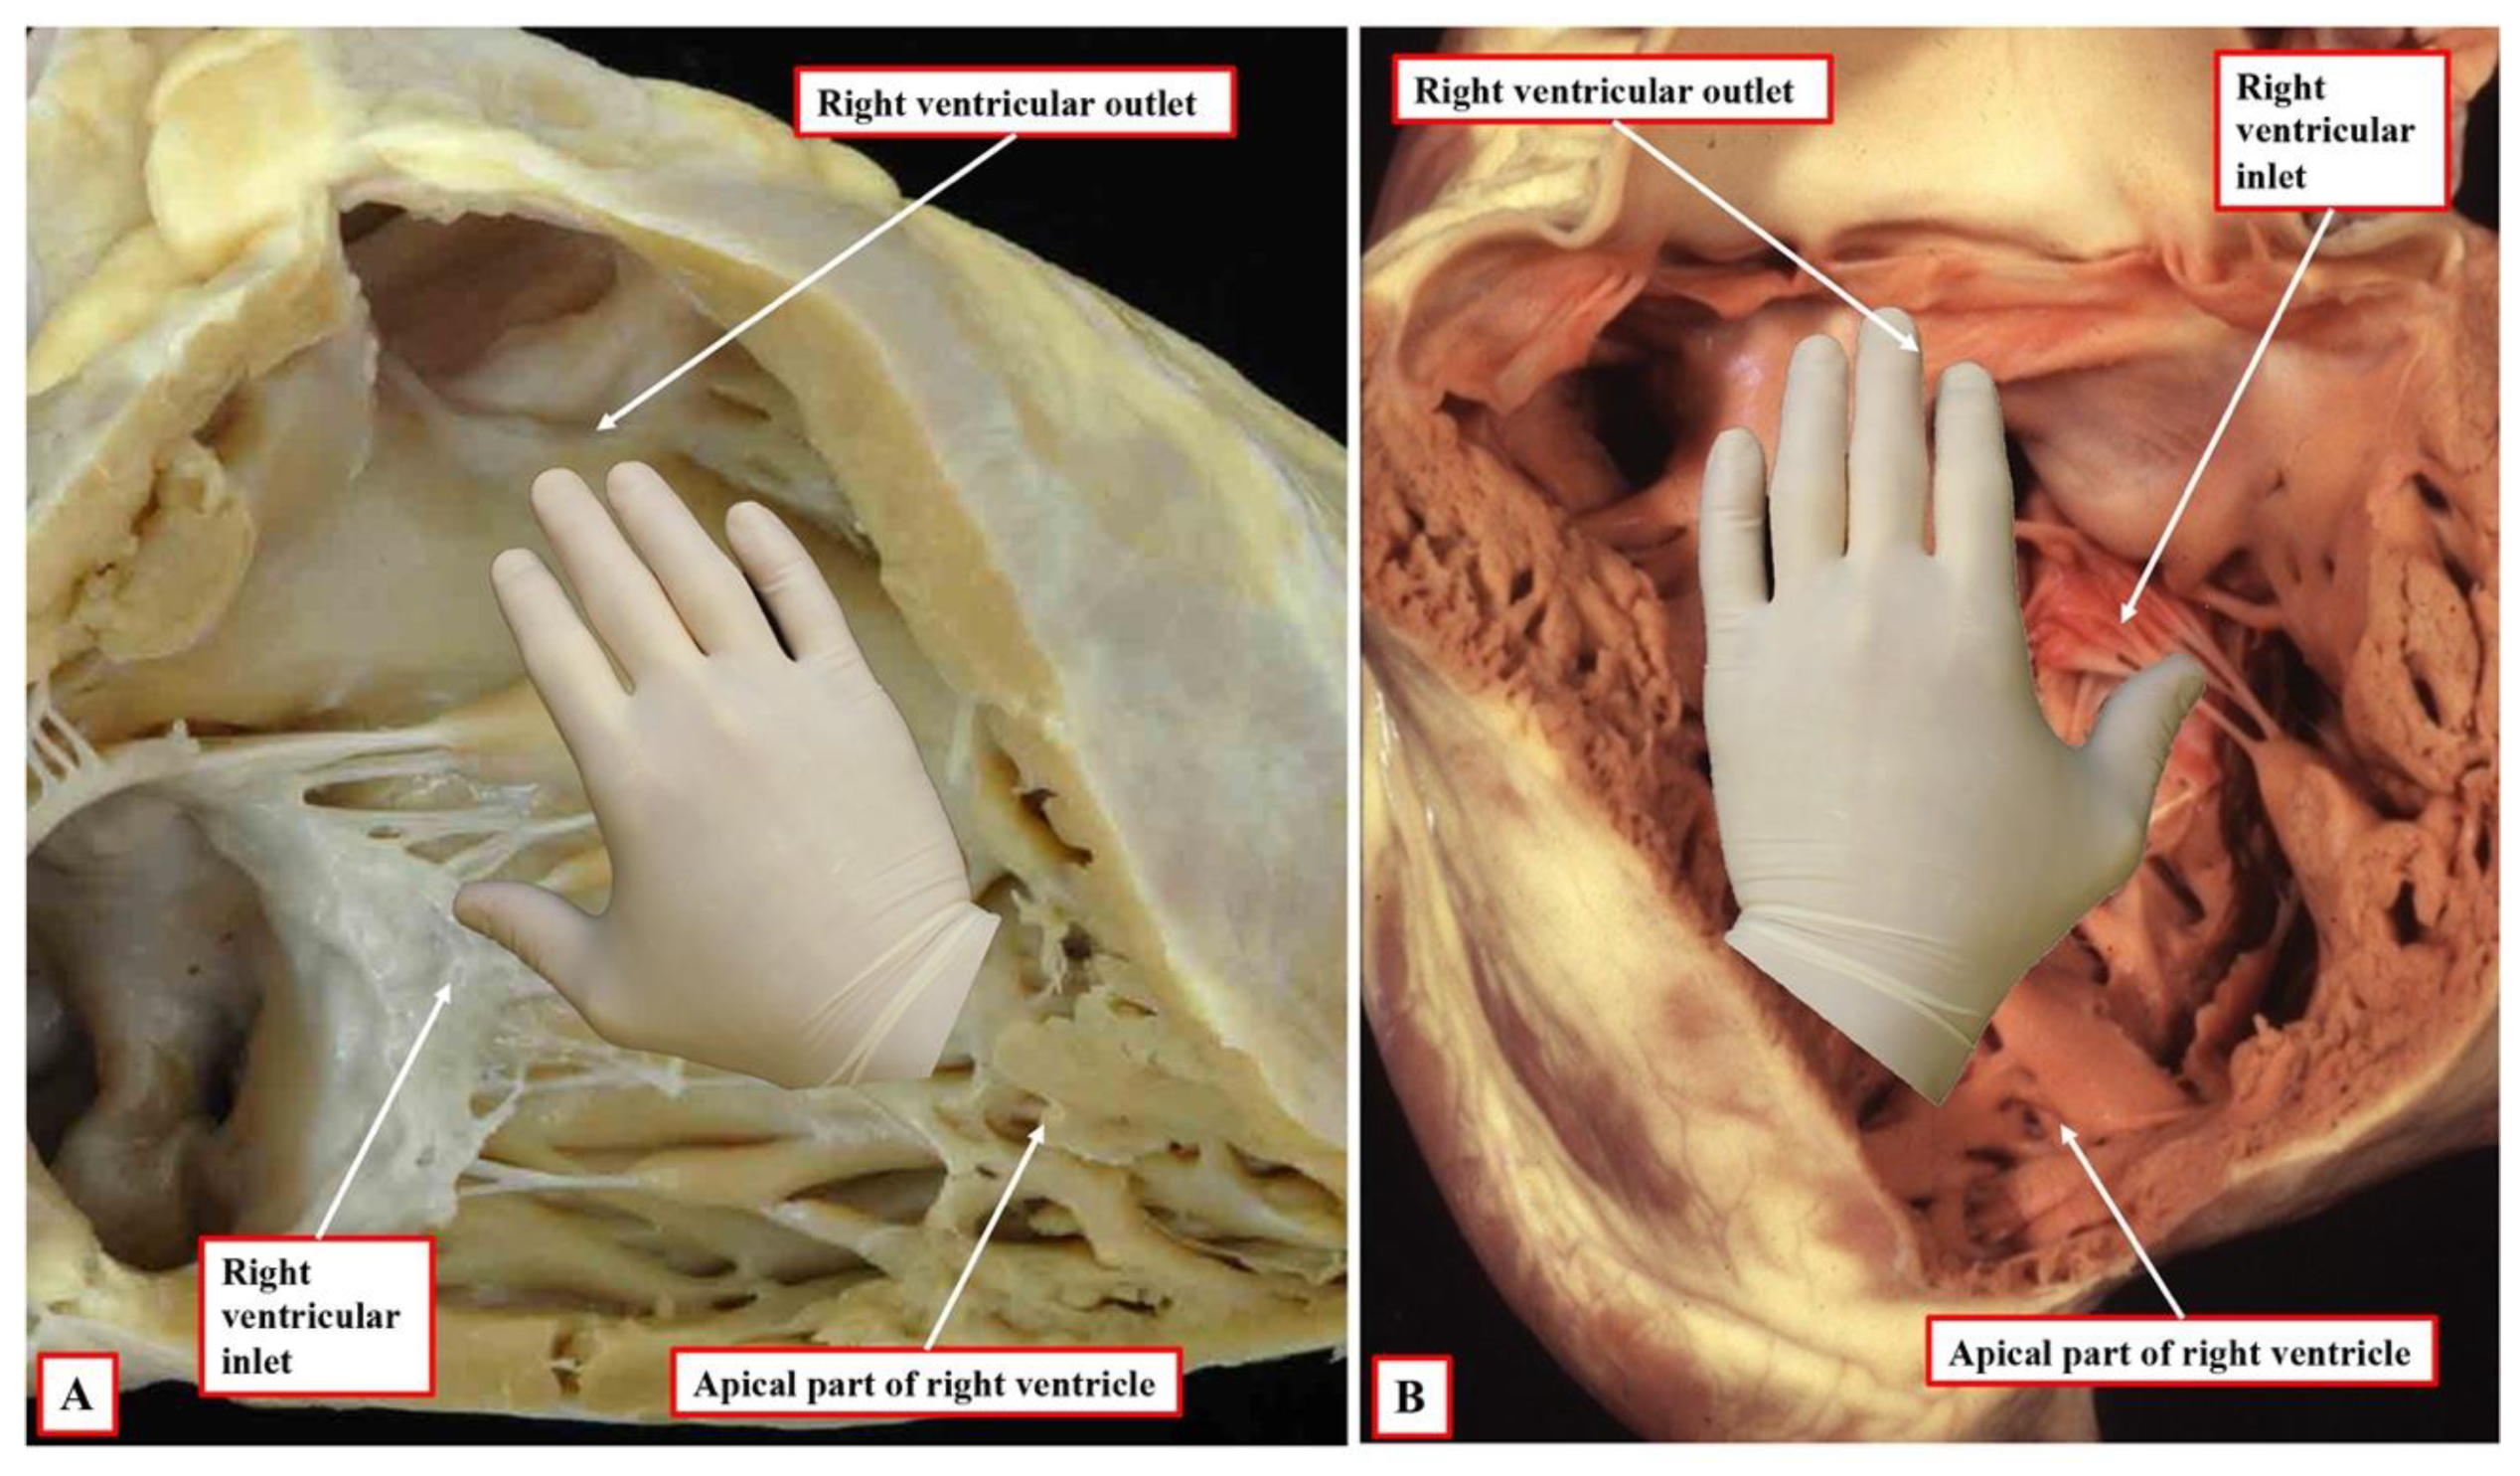

Figure 3B). It is the morphologically right ventricle, by convention, that is used as the arbiter of ventricular topology or chirality. The concept depends on the ability, figuratively speaking, to place the palmar surface of the hands on the septal surface of the right ventricle. The thumb is placed in the tricuspid valve, the wrist occupies the apical trabecular component, and the fingers extend into the ventricular outflow tract. In the normal heart, once the right ventricle has developed its own inlet (

Figure 3B), it is only the palm of the right hand that fits the septal surface of the morphologically right ventricle (

Figure 4A). In the setting of congenitally corrected transposition, in contrast, which is itself the consequence of the development of discordant atrioventricular connections, and when the atrial chambers are in their usual positions, it is only the palmar surface of the left hand that can be placed on the septal surface (

Figure 4B).

It follows, of course, that the left hand could be placed on the septal surface of the morphologically left ventricle in the setting of right-handed topology and the right hand when there is left-handed topology. Convention, nonetheless, has dictated that the right ventricle should be used as the landmark. It also follows that, should congenitally corrected transposition be found in the setting of mirror-imaged atrial arrangement, then the ventricular mass, almost without exception, shows right-handed topology. The caveat, however, is “almost without exception”. On very rare occasions, the ventricular topology is disharmonious with the fashion in which the cavities of the atrial chambers are joined to the ventricles. It is the feature of the flow pathways across the atrioventricular junctions, of course, which is used in the sequential segmental approach to define the segmental connections. Within the segmental approach, however, the so-called “alignments” must be inferred from the information provided within the segmental set. Thus, those with {S,D,*} are presumed to have concordance. This means that, in transposition {S,D,D}, the segmental notation indicates that the atrial and ventricular chambers are joined together in a morphologically appropriate fashion. In transposition {S,L,L}, the segmental notation would indicate that the atrial chambers are joined to morphologically inappropriate ventricles. This system, however, fails to account for disharmony between the morphology of the segments and the connections between them.